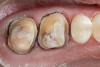

A patient presented with large amalgam restorations and recurrent caries on teeth Nos. 2 and 3 (Figure 2). After reviewing the treatment options, the patient chose all-ceramic crowns to restore the teeth. The specific all-ceramic crowns selected for the case were zirconia crowns. After completion of the crown preparations, soft-tissue retraction was achieved and the tooth surfaces were cleaned and dried (Figure 3). The teeth and soft tissues were isolated and lightly sprayed with a titanium-dioxide powder to create a reflective surface (). The powder provides contrast points for scanning to enhance recording the 3-D models and to improve the speed of recording.

Figure 2  Preoperative occlusal view of teeth Nos. 2 and 3.

Figure 2